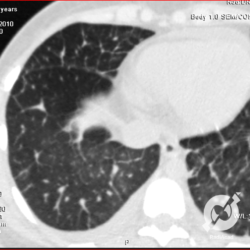

Opacidades em vidro fosco, espessamento septal liso, proeminência de estruturas venosas e derrame pleural bilateral.